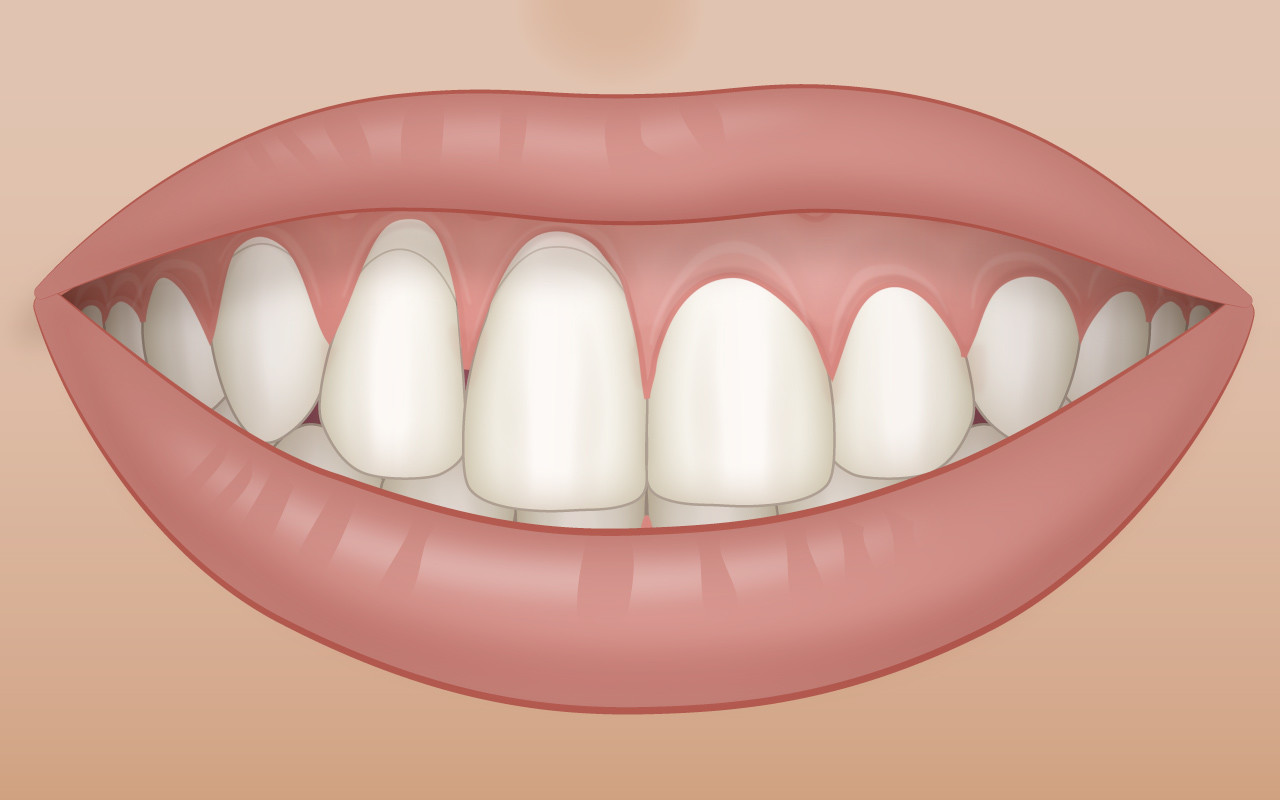

Probleme mit dem Aussehen (Ästhetik)

Zahnfleischrezessionen, welche an den sichtbaren Zähnen des Oberkiefers entstanden sind, werden oft auch aus ästhetischen Gründen als störend empfunden.

Durch die Rückbildung des Zahnfleischrandes entsteht der Eindruck, dass die betroffenen Zähne länger geworden sind. In der Regel bleiben diese Stellen für andere Mitmenschen unsichtbar. Erst beim Lachen zeigen Betroffene ihre Zahnfleischrezessionen – meist unfreiwillig.

In einigen Fällen können vorhandene Zahnfleischrezessionen auch aus ästhetischen Gründen einen stärkeren Leidensdruck auslösen. Dabei ist eine Beratung beim Zahnarzt und gegebenenfalls auch eine Überweisung zum Facharzt für Parodontologie angebracht.